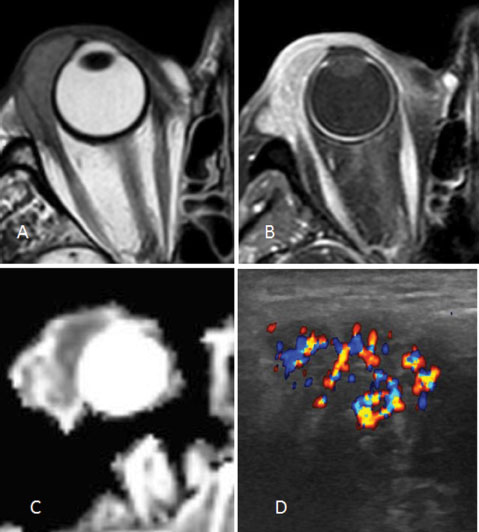

Finally, ubiquitous lesions are mainly lymphomas and inflammations, well defined or causing large orbital infiltration, sometimes spreading through the superior orbital fissure toward the cavernous sinuses and the meninges. Malignant lymphomas, often of B type, tend to be located at the anterior part of the orbit, display a very low apparent diffusion coefficient (ADC) on diffusion-weighted MRI and a nodular structure of low echogenicity, separated by highly vascularized septa on CDFI (Figure 2).

Figure 2

Lachrymal gland lymphoma T2-weighted (A), Post-contrast fat saturated T1-weighted (B), ADC (C), CDFI (D).